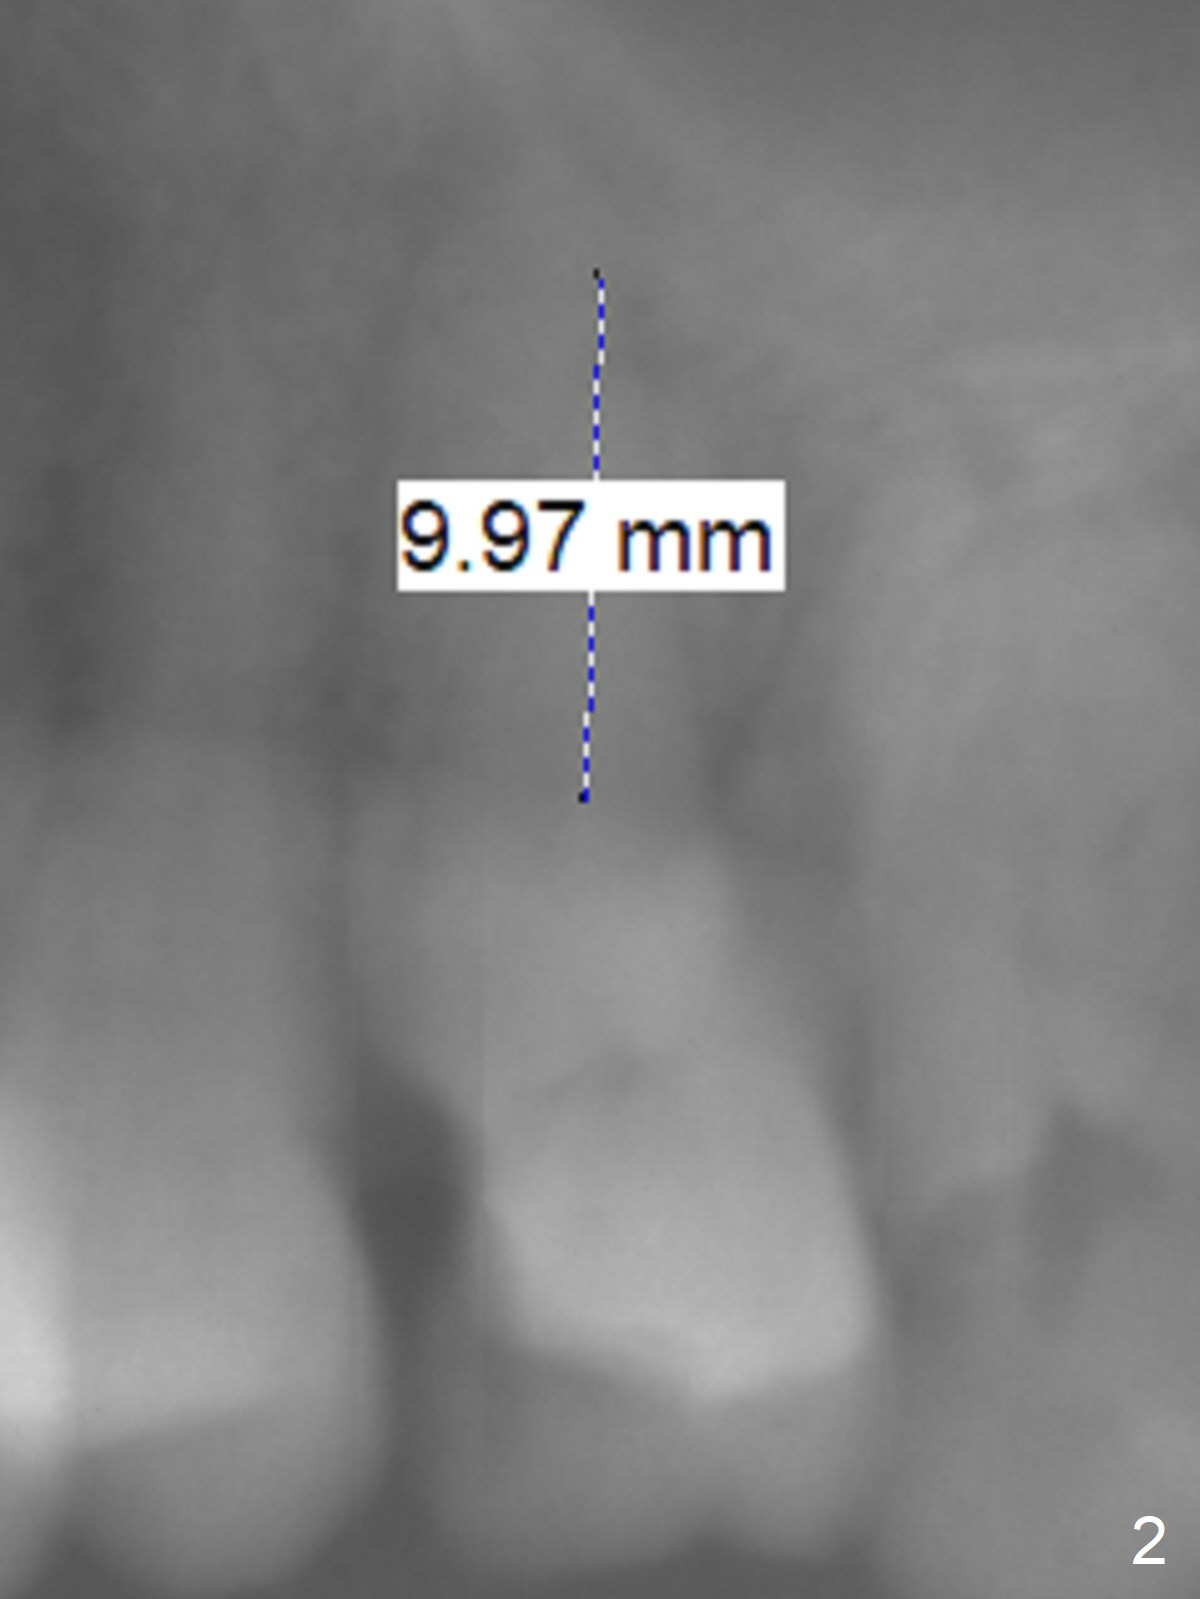

Osteotomy 1-2 mm from Sinus Floor

A 65-year-old woman cracks the tooth #14 prior to #4 implant (Fig.1). The height of the septum is ~ 10 mm; initial osteotomy depth will be 8.5 mm; 1-2 mm from the sinus floor. While increasing the drill size, check whether there is perforation on the side of the osteotomy apically. Since the patient is small, start low dose of X-ray.